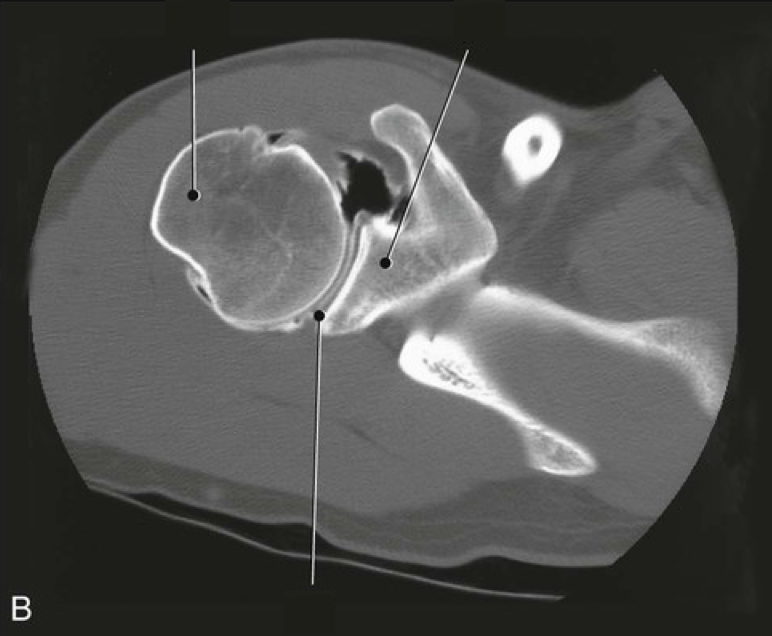

Question 3

Question

Label the image

Image:

2b92f734-ce7c-4b7f-841f-48114defa6ed (image/png)

Answer

acromion

humeral head

glenoid cavity

clavicle